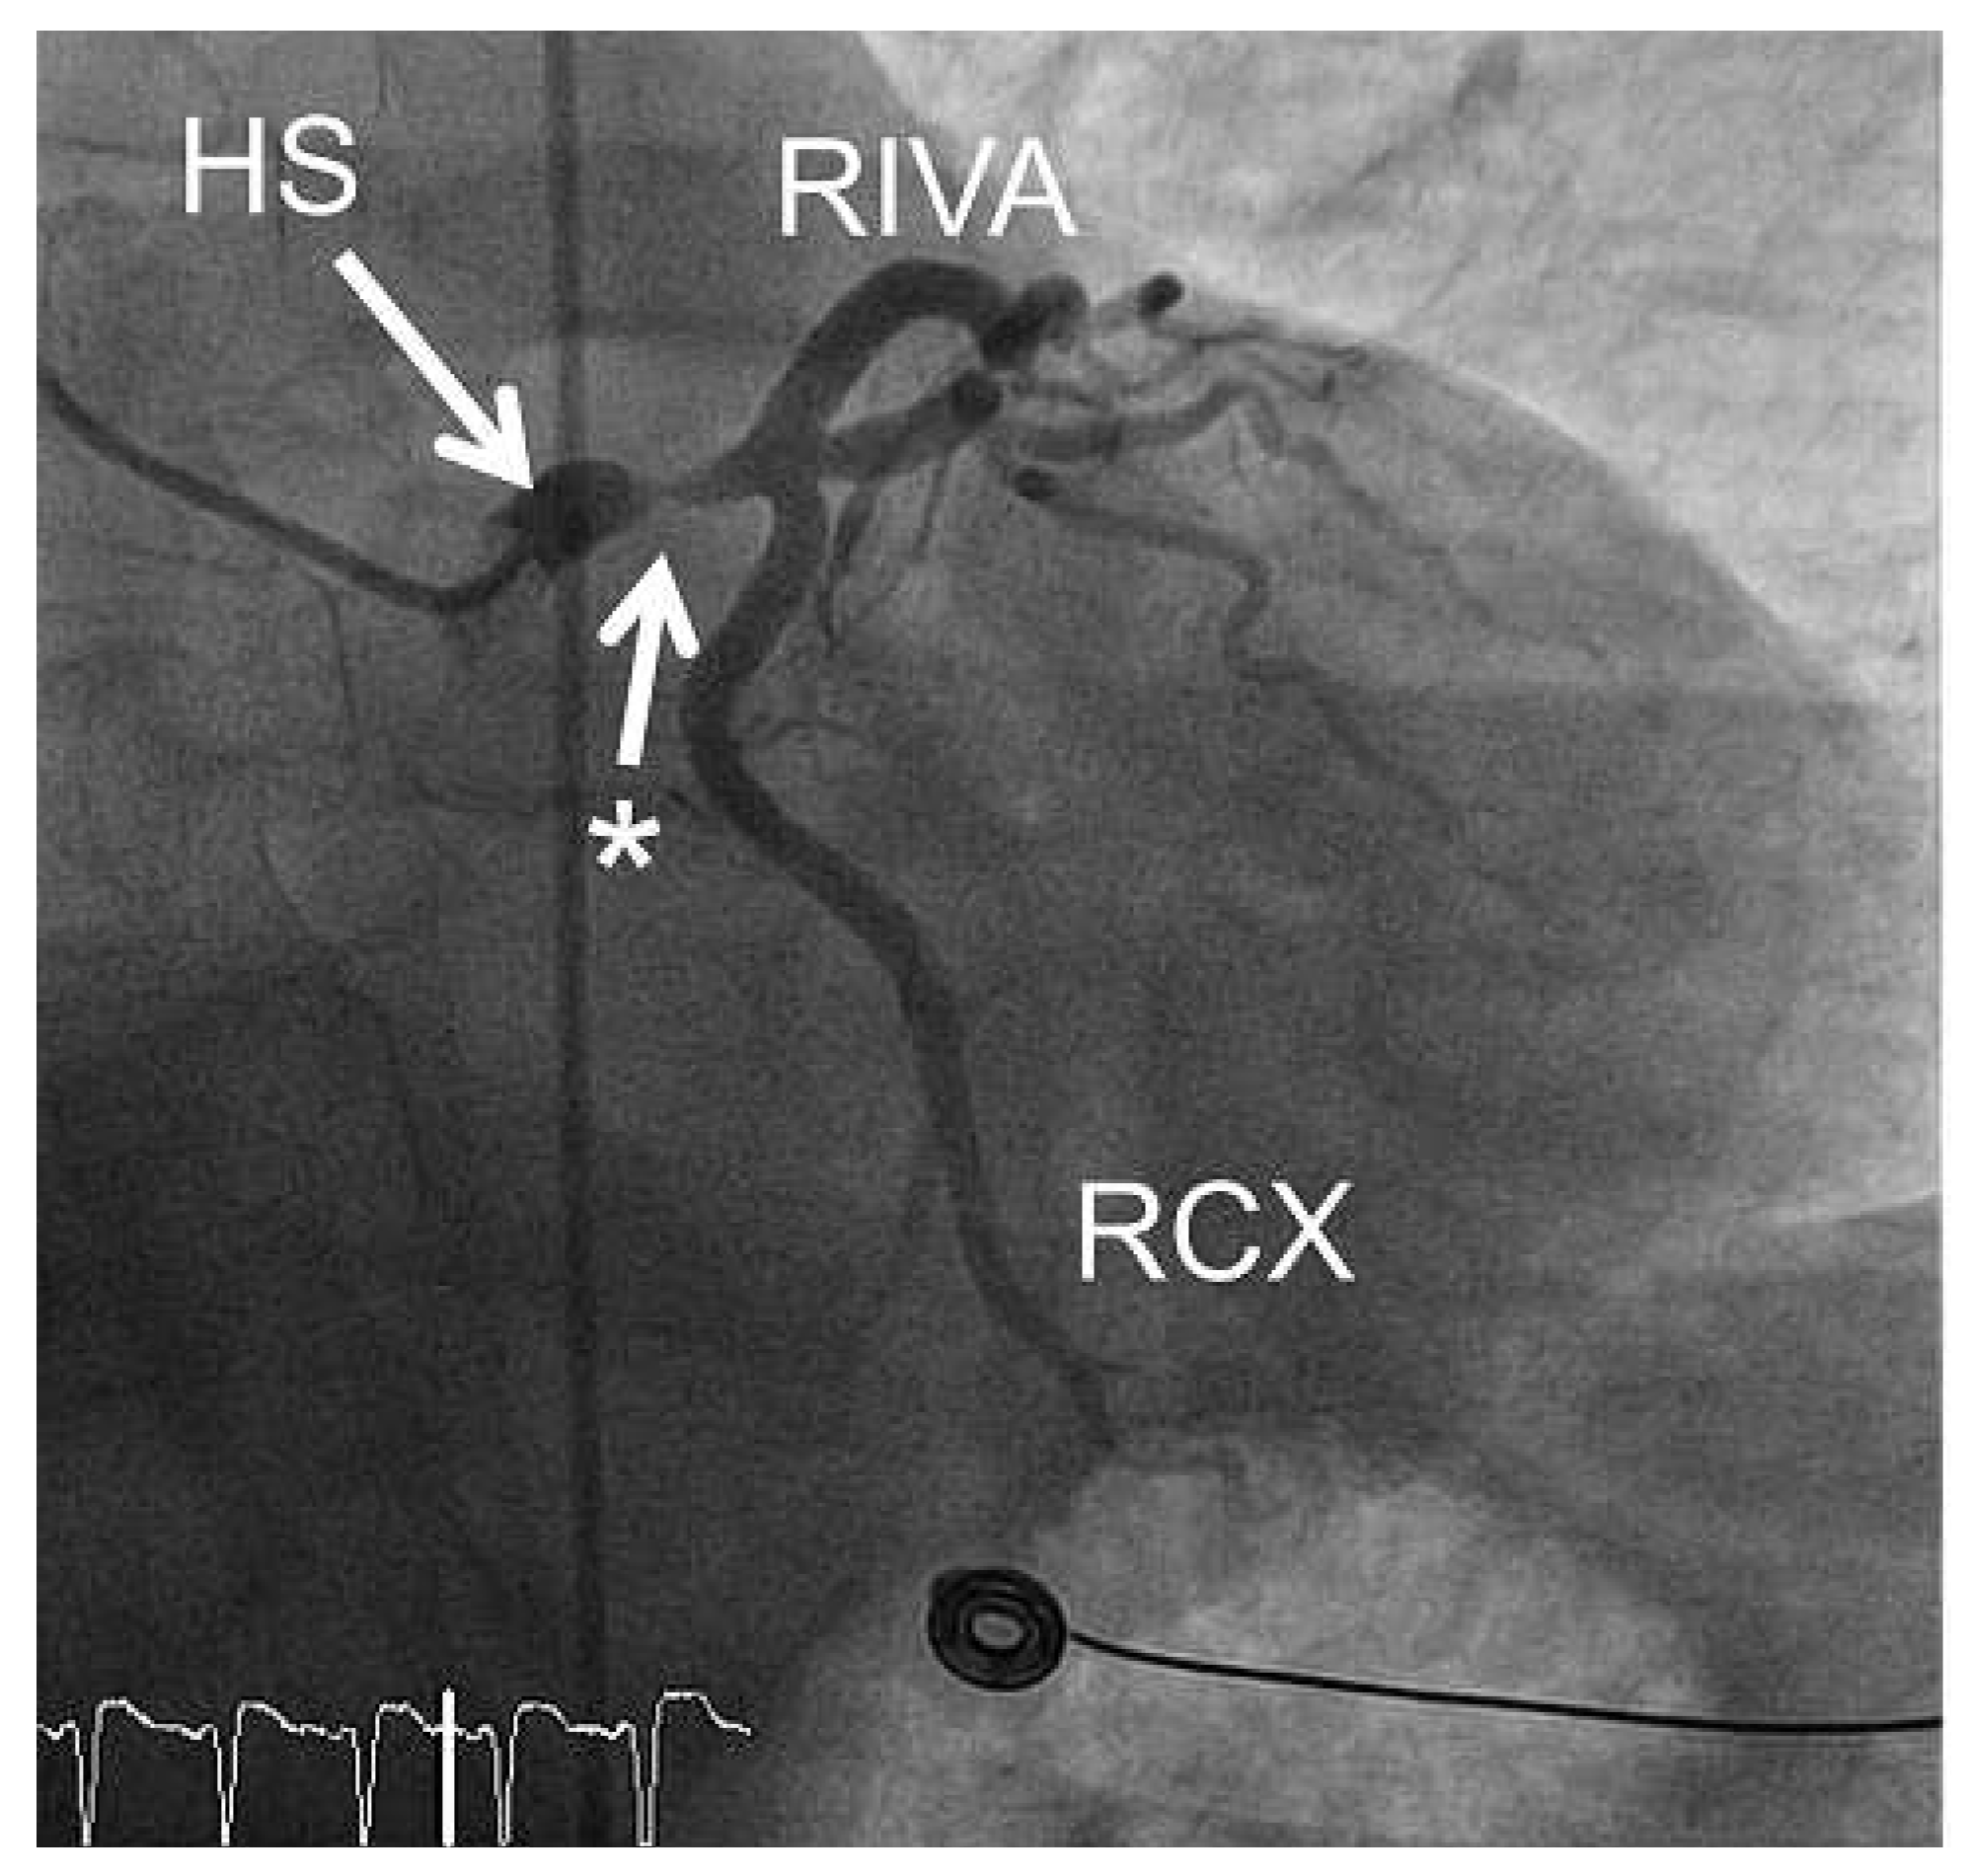

Echokardiographisch zeigte sich eine antero-apikale Hypokinesie mit einer eingeschränkten Pumpfunktion (LV-EF = 40%). Es wurde eine notfallmässige Koronar- angiographie durchgeführt, die eine isolierte Haupt- stammstenose zeigte (Abb. 3). Nach Einlage einer intraaortalen Ballonpumpe wurde eine notfallmässige aortokoronare Bypass-Operation mit Implantation der linken Arte- ria mammaria zum Ramus inter- ventricularis anterior (RIVA) und eines Venengraftes zum Mar- ginalast der Arteria circumflexa (RCX) durchgeführt.

Abbildung 3. Koronarangiographie der linken Kranzarterie des Patienten mit EKG 1 (Abb. 1): Es zeigt sich eine isolierte, hochgradige Hauptstammstenose (Stern). HS = Hauptstamm; RIVA = Ramus interventricularis anterior; RCX = Ramus circumflexus.